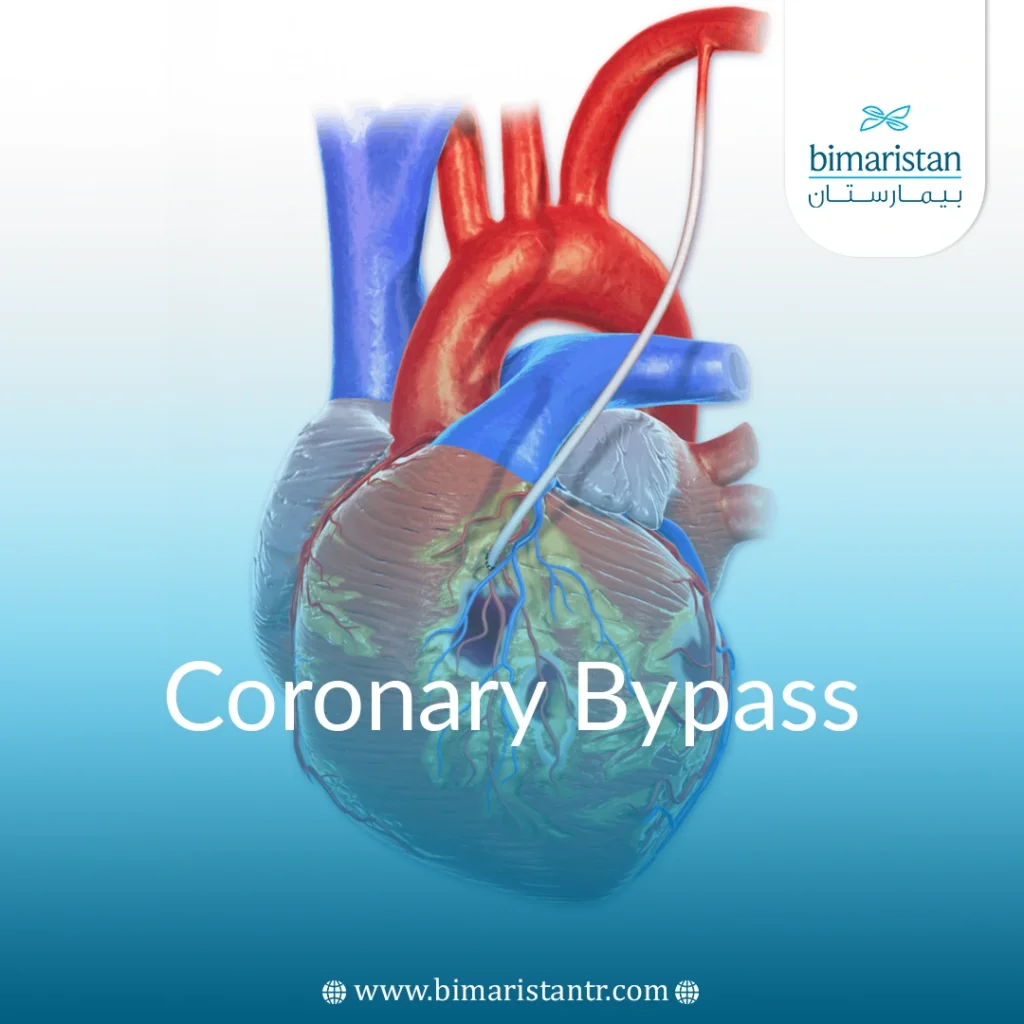

Bi-maristan.com